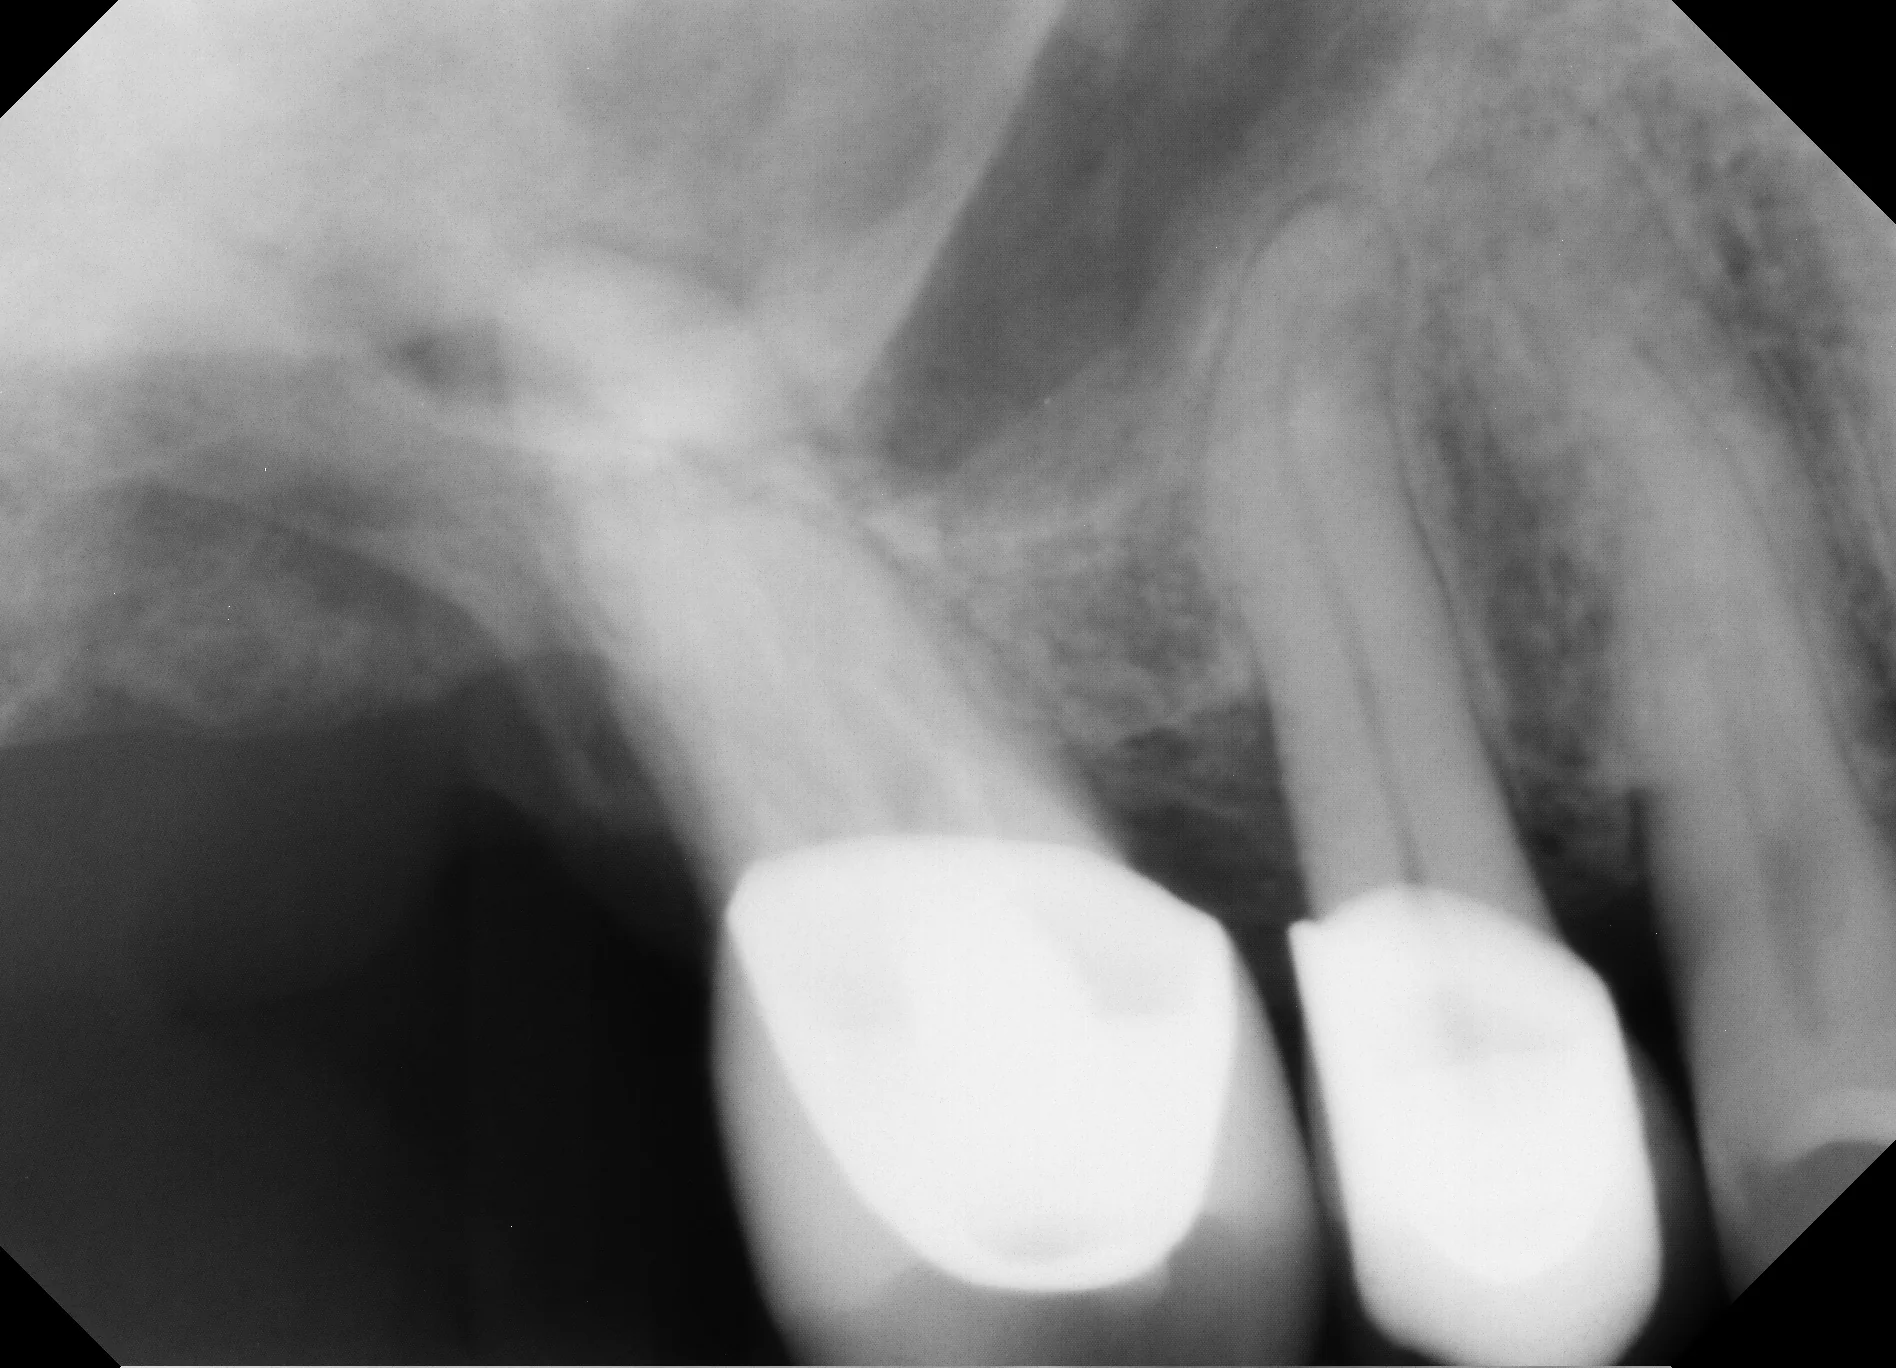

What the CBCT Showed

The 3D imaging revealed several findings that didn't fit a routine endo-perio presentation: calcification within the canal, furcation involvement, and — most concerning — irregular bone borders with cortical plate erosion. The borders weren't smooth the way you'd expect with a standard infection or cyst. They were ragged and ill-defined, which in rare cases can indicate malignancy.

• 2D Radiographs Can Be Deceiving: The periapical radiograph in this case appeared relatively normal. Without CBCT, the irregular bone destruction pattern would have been missed entirely.